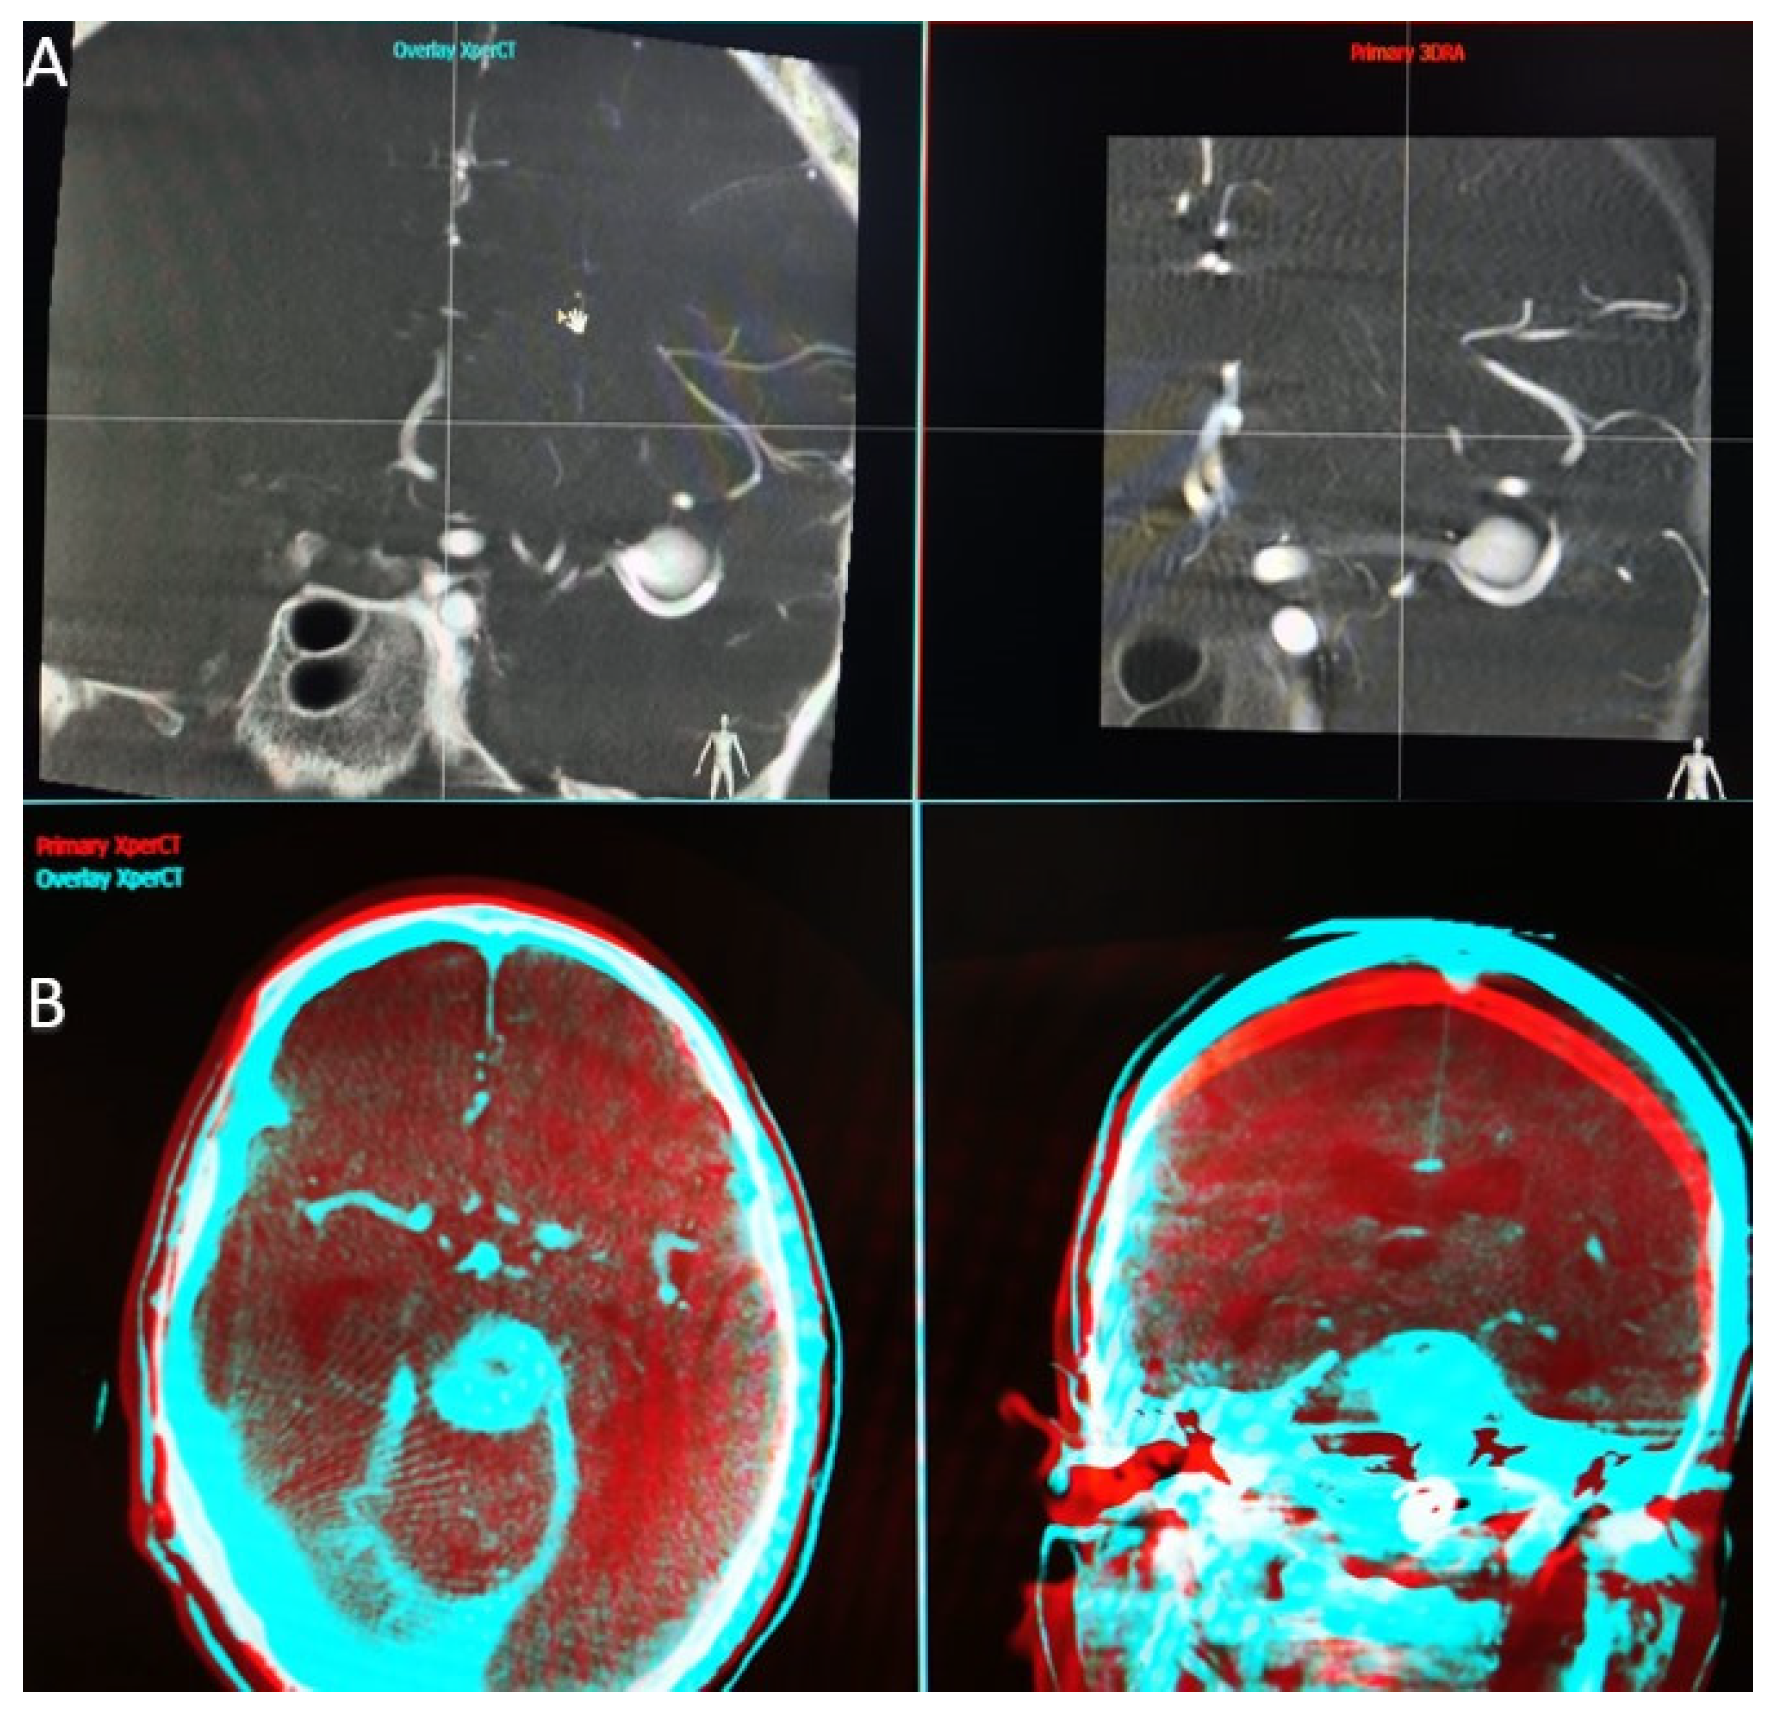

When the application that performs the overlay function is launched, we find a first interface that parallels the two volumes we have selected (Figure 1A). At this step, we have to choose a high Hounsfield unit object landmark (bone, endosaccular device, stent, coils) that we use to synchronize the volumes in all 3 planes (axial, sagittal, and coronal). Once the target point is placed in the same incidence on both volumes and in all 3 planes, we can open the second interface.

Figure 1.

(A) Workstation first interface that parallels the two volumes we have selected. (B) Workstation second interface, red—primary volume, and blue—overlay volume, two spatial planes at the same time.

In the second interface (Figure 1B), the screen is also split into two parts, and we have the possibility to analyze the superposition of the two volumes in different colors (red—primary volume, and blue—overlay volume) and in two spatial planes at the same time. Both volume images were presented in different colors and in the same window as the orthogonal multi-planar reconstruction (MPR) images in axial, sagittal, and coronal orientations. We can now manually correct angulation errors (higher in patients without general anesthesia) and accurately calibrate the anatomy, thereby compensating for vascular anatomical changes due to stent placement.